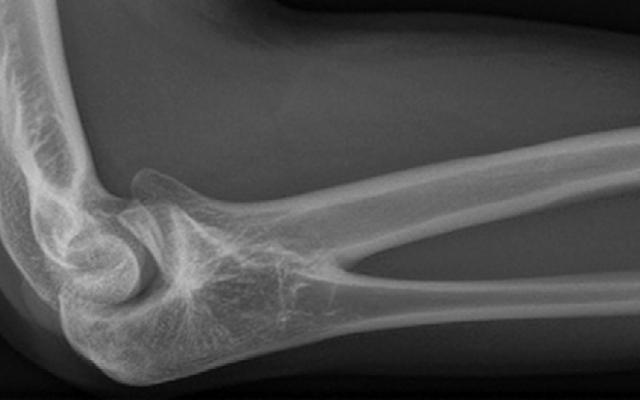

Een 18-jarige man werd via de huisarts verwezen naar de polikliniek Orthopedie met verminderde beweeglijkheid van de rechter arm, die vanaf de kinderleeftijd aanwezig was. De patiënt had geen pijnklachten, maar wel hinderlijk functieverlies bij sportuitoefening. Zijn broer had hetzelfde probleem aan beide armen. Bij lichamelijk onderzoek waren pro- en supinatie van de rechter onderarm volledig afwezig, met een neutrale stand van 5˚ pronatie (figuur a en b). Aan de linker arm was er bij actieve beweging 50˚ pronatie en 85˚ supinatie mogelijk. Conventioneel röntgenonderzoek toonde een benige verbinding proximaal tussen de radius en de ulna (figuur c), een…